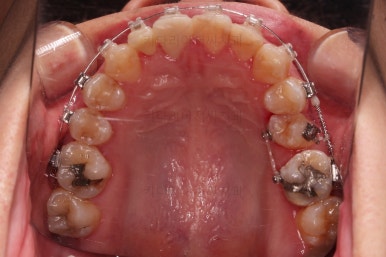

임플란트를 위한 기본 셋팅이 거의 완료되었습니다.

이 모습까지 13개월 걸렸네요.

굉장히 급한 마음으로 달려왔습니다.

지금부터는 임플란트, 보철 등을 진행하며 연산동치아교정은 보조적으로 진행하게 됩니다.